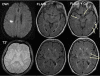

Methods: We followed-up patients with nondisabling lacunar or cortical stroke and BBB permeability magnetic resonance imaging after their original stroke. Approximately 3 years later, we assessed functional outcome (Oxford Handicap Score, poor outcome defined as 3-6), recurrent neurological events, and white matter hyperintensity (WMH) progression on magnetic resonance imaging.

Results: Among 70 patients with mean age of 68 (SD ± 11) years, median time to clinical follow-up was 39 months (interquartile range, 30-45) and median Oxford Handicap Score was 2 (interquartile range, 1-3); poor functional outcome was associated with higher baseline WMH score (P<0.001) and increased basal ganglia BBB permeability (P=0.046). Among 48 patients with follow-up magnetic resonance imaging, WMH progression at follow-up was associated with baseline WMH (ANCOVA P<0.0001) and age (ANCOVA P=0.032).